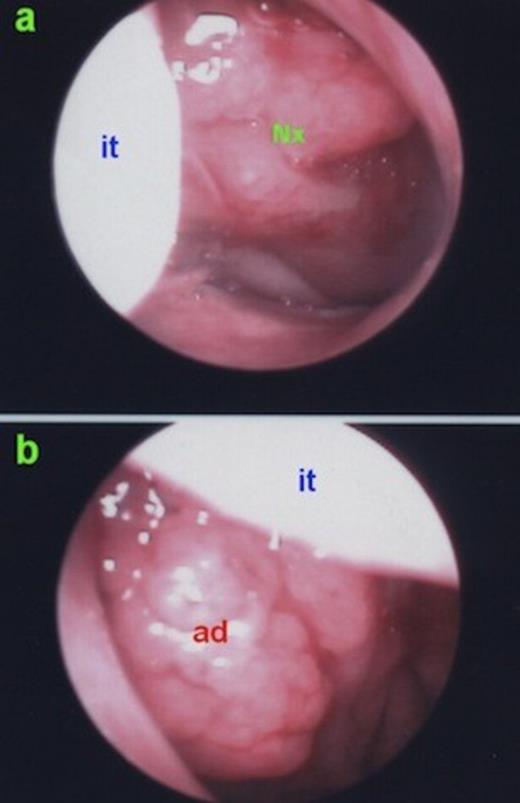

A computed tomography (CT) was performed and a left sided mass in the inferior meatus which has demonstrated central calcification was reported (Figure 1). Mild mucosal hypertrophy was present in the left ethmoid and maxillary sinuses, accompanied with ipsilateral asymmetric adenoid hypertrophy (Figure 2).

Asymmetric adenoid hypertrophy, more prominent on the left side. ad: adenoid hypertrophy